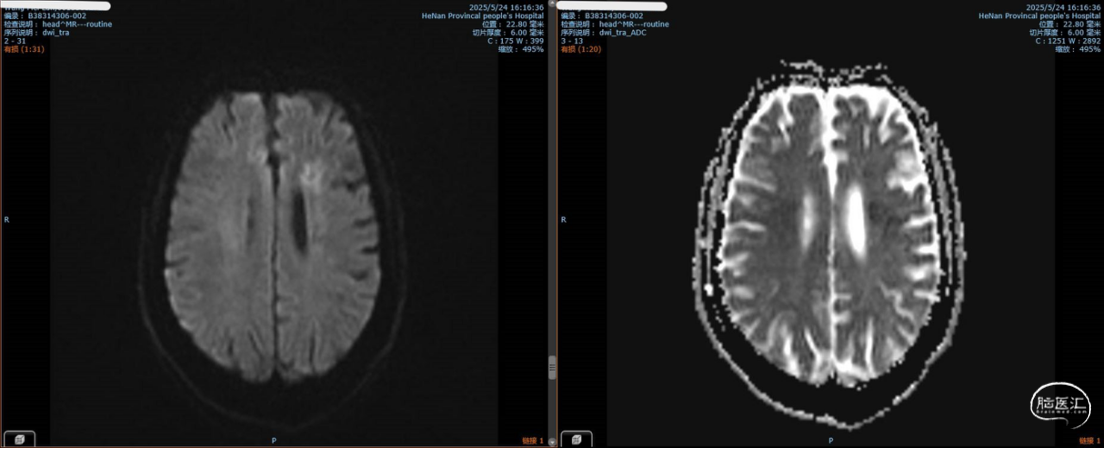

MRI提示左侧额顶叶侧脑室旁亚急性、慢性早期脑梗死。

2025-7再次入院,术前MRI无急性期脑梗死。